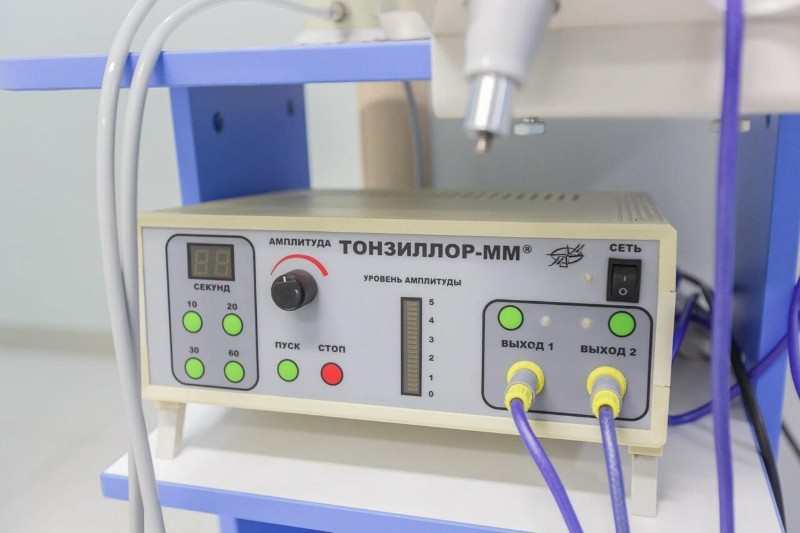

02.12.2025Новая программа обследования позволяет точно оценить состояние носоглотки, выявить скрытые инфекции и подобрать эффективную тактику лечения.

02.12.2025Новая программа обследования позволяет точно оценить состояние носоглотки, выявить скрытые инфекции и подобрать эффективную тактику лечения. -